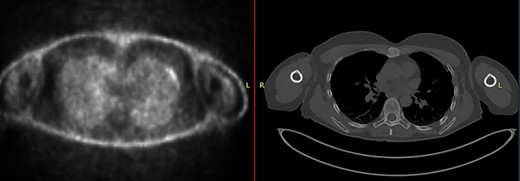

The first case at our institution was a 39-year-old woman who had a history of left breast carcinoma treated with left mastectomy, axillary node clearance and immediate reconstruction under the care of the breast team 3 years prior to presentation. She had no significant co-morbidities. Her past surgical history consisted of the aforementioned oncological operation, appendicectomy and cholecystectomy. She had completed adjuvant oncological therapy in the form of chemoradiotherapy and maintenance hormonal therapy. Her post-operative histology was consistent with a fully excised left breast ductal carcinoma and spread to three out of nine lymph nodes. Due to positive oestrogen receptor-2 status, she had been placed on hormonal therapy. She re-presented with chest wall and sternal pain and subsequent computer tomography (CT) imaging demonstrated a suspicious looking lytic lesion in the mid-sternum (Fig. 1). She underwent a biopsy of this lesion, which confirmed the diagnosis. She had been taking opioid medication for the pain. She was seen in clinic and counselled for partial sternectomy and reconstruction. She underwent partial sternectomy and underwent reconstruction with vertical and horizontal Synthes® plates. Her post-operative recovery was unremarkable. Post-operative histology was consistent with metastatic breast carcinoma completely excised. The recovery was uncomplicated and the patient was seen in clinic with a satisfactory chest radiograph demonstrating the sternal Synthes® plates (Fig. 2).

CT–PET demonstrating increased metabolic activity within the sternal lesion.